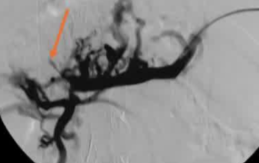

该程序包含以下步骤: 经脾脏入路:在超声引导下,刺穿脾静脉内的一个实质内分支。 在通过脾静脉造影确认了静脉通路后,导管和导丝被推进,以穿过脾静脉并抵达血栓化的门静脉。在门静脉/右门静脉分支处放置圈套器,为TIPS穿刺精准定位。TIPS穿刺圈套器,并穿过圈套器完成TIPS

步骤: 鉴于慢性血栓形成的复杂性: 一种经脾脏途径的门静脉再通术(PVR)。 随后是经颈静脉肝内门体分流术 。

结果:术后影像学检查显示门静脉和脾静脉的血流情况有所改善,且残留血栓极少。

通过经颈静脉肝内门体分流术(TIPS)治疗慢性门静脉血栓时所涉及的技术复杂性和决策难题,尤其是在标准方法因血栓程度过重而无法实施的情况下更是如此。 采用脾经脏穿刺术治疗门静脉高压症的方法证明能够有效克服这些难题,从而成功实施了经颈静脉肝内门体分流术(TIPS)。 PVR-TIPS 作为一线治疗方案:PVR-TIPS 为慢性门静脉血栓的治疗提供了一种技术上可行的解决方案,克服了标准 TIPS 安装所面临的难题。 持久效果:该干预措施不仅恢复了门静脉的血流,而且在后续随访中还显示出持续的通畅性以及血栓的完全消散。